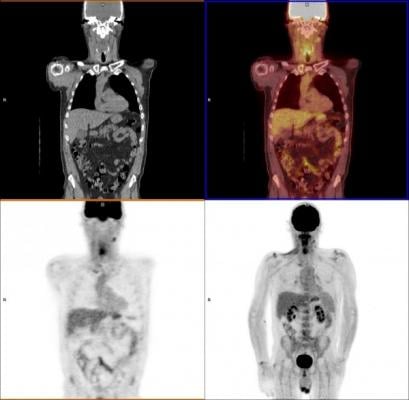

The use of positron emission tomography–computed tomography (PET-CT) scans for image-guided surveillance meant that routine post-treatment operations were no longer necessary, and can now be better targeted to the right areas in those 20 percent of patients who still have persistent cancer.

Prof. Hisham Mehanna, from the Institute of Head and Neck Studies and Education (InHANSE) at the University of Birmingham, explained, “After treatment, remaining cancer cells play something akin to hide and seek. Our study shows that using this PET-CT scan we can hunt them down, find them and remove them effectively.”